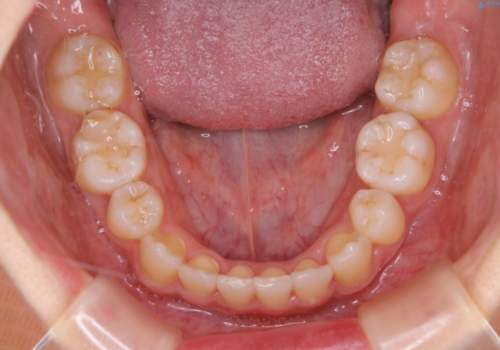

- 元々は海外でワイヤー矯正を行っていたが、コロナ禍で海外への往来が難しくなり、治療を中断せざるを得なくなってしまった方です。

ご本人のご希望により、インビザラインによる治療を行いました。

ブラケット除去直後に目立っていた下顎前歯部の大きなブラックトライアングルもあまり目立たなくなり、大変喜んでいただけました。